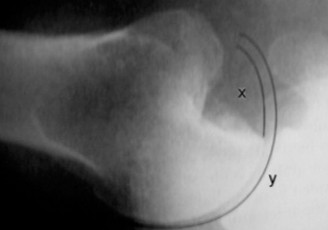

2. الأشعة المقطعية (Computed Tomography - CT Scan) مع إعادة البناء ثلاثي الأبعاد (3D Reconstructions)

نظراً للطبيعة المزمنة للخلع (أكثر من 3 أسابيع)، تُعد الأشعة المقطعية ضرورية لتقييم دقيق لمدى فقدان العظم وتوجيه التخطيط الجراحي. تكشف الأشعة المقطعية عن:

- فقدان عظم الحُق (Glenoid Bone Loss): تُظهر الأشعة المقطعية عيباً عظمياً كبيراً في الجزء الأمامي السفلي من الحُق، والذي يُقدر بنسبة 25-30% من عرض الحُق. يُعرف هذا بـ "آفة بانكارت العظمية" (Bony Bankart lesion).

- عيب رأس عظم العضد (Hill-Sachs Lesion): تُظهر الأشعة المقطعية أيضاً آفة هيل ساكس كبيرة في الجزء الخلفي العلوي من رأس عظم العضد، والتي تُعرف بأنها "متداخلة" (Engaging) مع عيب الحُق.

- المسافة المفصلية: قد تُلاحظ تغيرات تنكسية خفيفة في المفصل، مما يدل على مزمنة الحالة.

(الشكل 2: إعادة بناء مقطعي في المستوى الإكليلي يوضح فقدان العظم في الحُق (بانكارت العظمي) ورأس العضد المخلوع أمامياً.)

(الشكل 3: إعادة بناء ثلاثي الأبعاد بالأشعة المقطعية يبرز العيب الأمامي في الحُق وآفة هيل ساكس المقابلة على رأس العضد.)